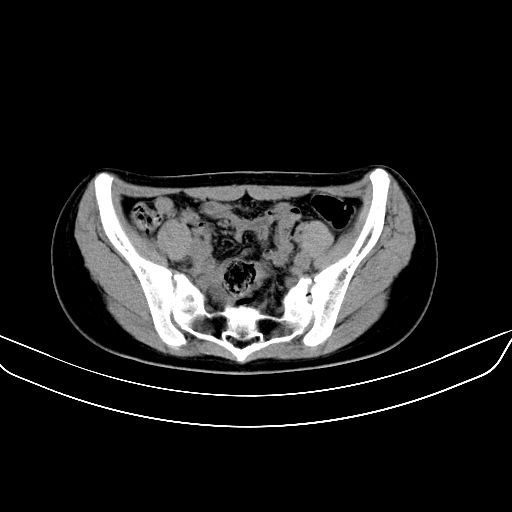

以下是引用zsl6918在2008-7-11 21:40:00的发言:[br]双侧骶髂关节骨质破坏以下三分之一为主,符合强直性脊柱炎表现

以下是引用zhangzhongshou在2008-7-11 21:41:00的发言:[br]患者是女性,hla-b27抗原(—),首先不太考虑强直性脊柱炎,建议查类风湿因子,骶髂关节改变考虑类风湿性关节炎可能性大,建议进一步检查。